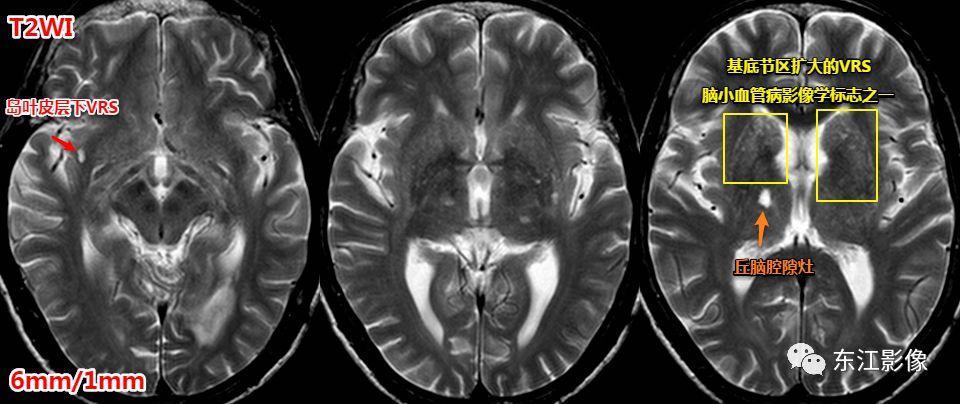

血管周围间隙常见分布。

前穿质区VRS经典CT、MRI影像。

注意,扩大的血管周围间隙也是脑小血管病的影像学标志之一,但并非所有扩大的血管周围间隙均与脑小血管病有联系。

一般认为,基底节区中上区域扩大的血管周围间隙多与脑小血管病有关系。

基底节区扩大的血管周围间隙,丘脑腔隙灶典型影像,均为脑小血管病影像学标志。

前穿质区扩大的血管周围间隙经常被误诊为脉络膜裂囊肿、腔隙性梗死灶。

前穿质区是血管周围间隙最常见的部位,主体位于脑实质,层面合适时可见尖角(==》多方位观察)。